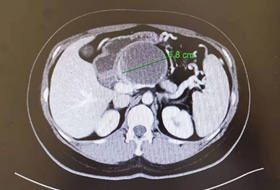

图:CT发现胰腺上直径7cm的囊肿

经过增强CT的检查,医生发现李女士的胰腺囊肿位于体部,直径7厘米左右,囊壁有结节样凸起。结合李女士之前并没有胰腺炎及胰腺外伤的病史,龚伟主任判断李女士的胰腺囊肿并不简单,极有可能是胰腺粘液性囊腺瘤,这是一种存在癌变倾向的胰腺囊性肿瘤,需要尽快手术治疗。